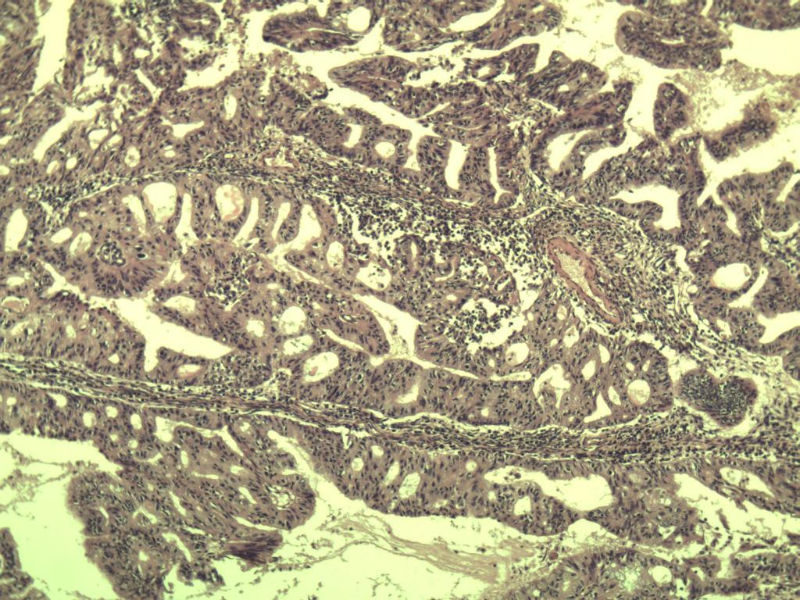

女,57岁,全切子宫一个,宫体体积 9 × 8 × 7 cm3,肌壁厚 2.5 cm,内膜菲薄,部分区域增厚达 0.4 cm(约3*2.5cm区域)。 请问各位老师  这个可以诊断子宫内膜癌了吧?      深肌层没有看到浸润。

患者因"发现下腹部包块1月多"入院  宫体体积 9 × 8 × 7 cm3,肌壁厚 2.5 cm,内膜菲薄,部分区域厚 0.4 cm(约3*2.5cm)。宫颈结构不清,长约 2.5 cm,表面欠光滑。临床诊断宫颈宫腔积液.

宫内膜样腺癌

筛状、迷路样结构

间质消失或者纤维性间质

子宫内膜样腺癌

高分化子宫内膜样癌。浸润浅肌层(深度<1/3肌层)。根据FIGO2009分期,子宫内膜癌局限于内膜层和<1/2肌层,都属于IA期。二者处理不再区别对待。